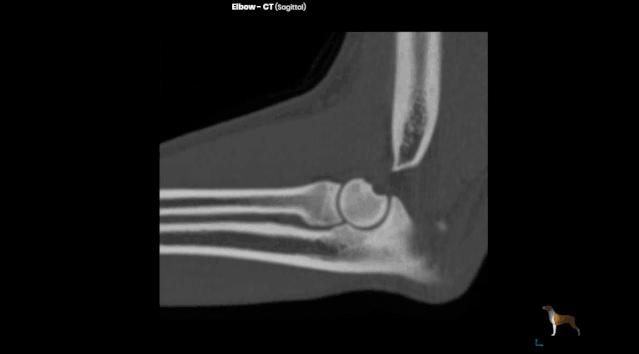

下图是狗的肱骨(上腕骨)结构,肱骨末端的那个洞就是冠状窝,与下方尺骨的鹰嘴窝构成了前肢的肘关节。

但猫就不同了......

猫咪的肱骨远端仅有一个附孔,孔中有神经穿过 ,手术稍有不慎就会损伤神经,对医生技术的要求非常高。

CT也是一种 X 线检查,它能对骨折部位进行多层的扫描,提供每一层的截面图像,使骨折的图像呈现避免了其他组织的干扰,更清楚地显示出来。在普通的X线片上显示不出来骨折都能在CT片上清楚地显示。